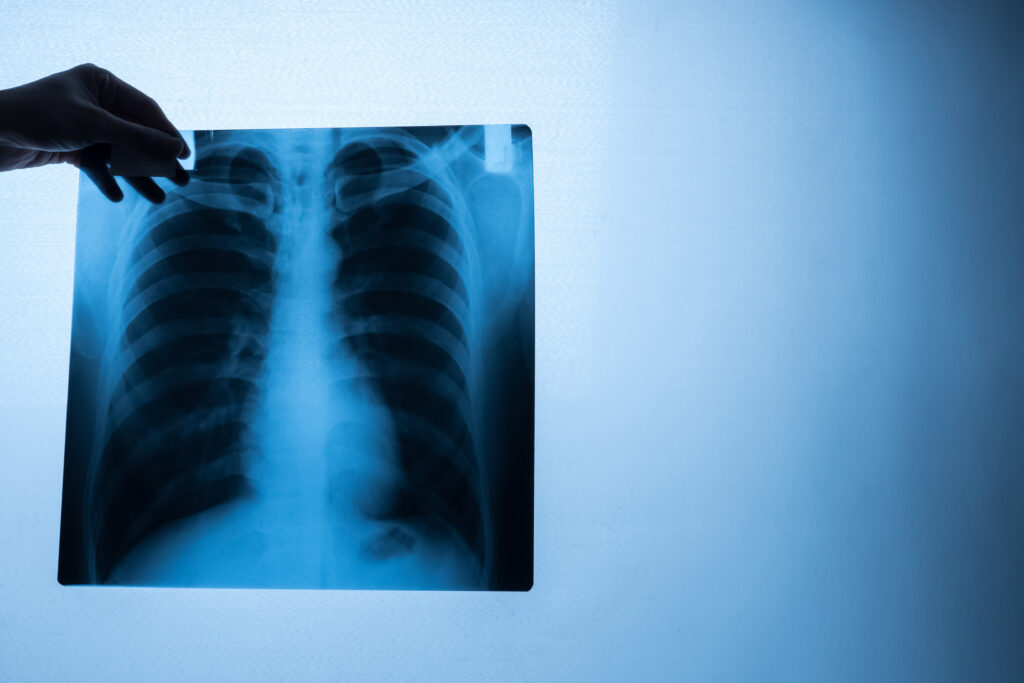

En Clínica Express ofrecemos rayos X de abdomen en Panamá con tecnología moderna para evaluar órganos como el estómago, intestinos y estructuras abdominales, permitiendo un diagnóstico rápido y confiable.

La radiografía de abdomen es un estudio clave para detectar obstrucciones, cálculos, acumulación de gases y otras afecciones digestivas.